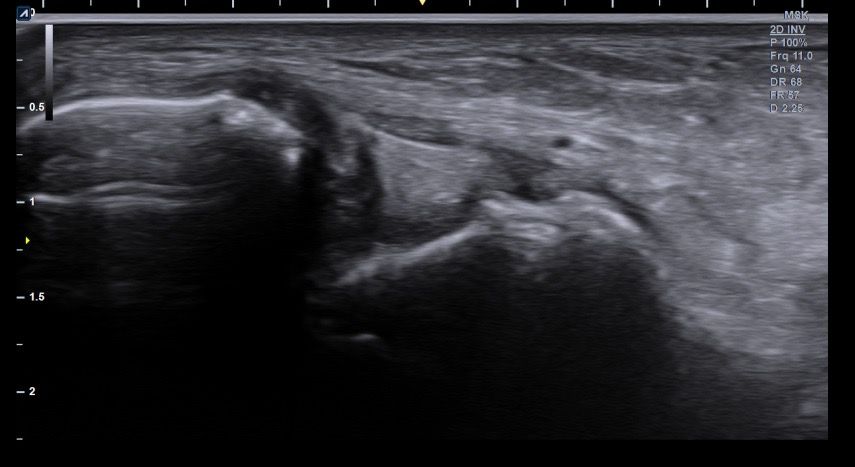

복숭아뼈 미세골절 초음파 사진 관련 질문

발목 접지른 후 치료받는 중인데요 복숭아뼈 미세골절이라고 하셨네요 3월 1일 다친뒤네 3월7일 병원방문후에 위에 초음파랑 엑스레이 촬영했고요 그뒤 반깁스 중입니다. 위에 엑스레이 상에선 안나오는데 초음파 사진에선 미세골절이 맞을까요? 골절이 경미한 수준인지 아니면 중한 건지 궁금합니다 그리고 다음주에 병원 방문 후 초음파 또 촬영하기로 했는데 그때 반깁스도 풀 수 있을까요??

• 1번 째 사진

• 2번 째 사진

• 3번 째 사진

• 4번 째 사진

발목의 복숭아뼈에 미세골절이 의심되는 경우, 엑스레이에서는 미세골절이 잘 보이지 않을 수 있습니다. 엑스레이는 큰 골절을 잘 확인하지만, 미세한 골절이나 염증 반응은 잘 나타나지 않기 때문이죠. 초음파는 조직의 변화를 보다 민감하게 감지할 수 있기 때문에, 미세골절을 발견하는 데 도움을 줄 수 있습니다. 초음파에서 미세골절이 확인되었다면, 이는 경미한 골절일 가능성이 높아요. 하지만 골절의 정확한 상태나 치유 과정을 판단하려면 정밀 검사가 필요하죠